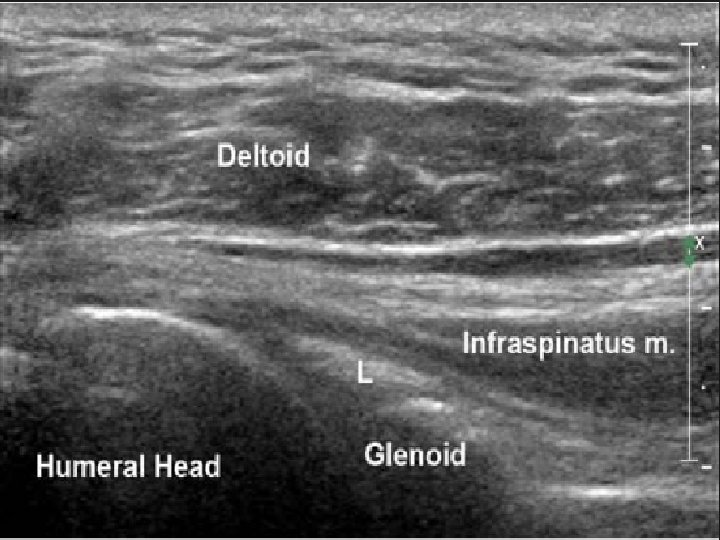

Girişimsel Ne Yapabiliriz ? • Glenohumeral eklem içine steroid en sık uygulanan yöntem • Glenohumeral eklem içi steroid + supraskapuler sinir bloğu • Pulsed Radyofrekans (PRF) yeni , non-nörodesturiktif

Neyi Amaçladık ? Kronik omuz ağrısı olan hastalarda ultrasonografi eşliğinde uygulanan omuz eklem içi steroid enjeksiyonu + supraskapuler sinir bloğu supraskapuler sinir pulsed radyofrekans işlem başarısı, etki süresi ve hasta memnuniyeti